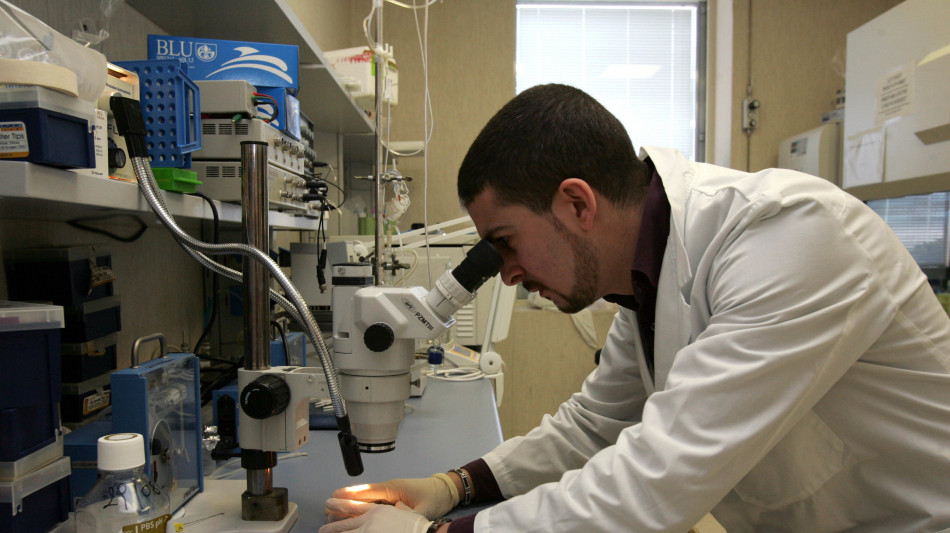

Modelli su misura della Sla per capire gli effetti dei farmaci

Ottenuti in laboratorio da cellule staminali